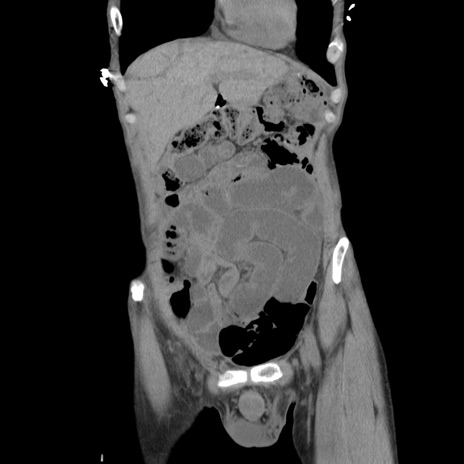

横断像

症例11(冠状断像)

【症例】 60歳代男性

【主訴】 下腹部痛

【現病歴】 本日夜中より下腹部痛の症状認め、受診。

【既往歴】 膀胱癌(膀胱全摘+尿管皮膚瘻術) 、胃癌術後

【身体所見】 BT 35.3℃、PR 58/min、BP 136/98mHg、腹部平坦、軟、腸蠕動音±、ストマ留置あり、左上腹部~正中部に圧痛あり、反跳痛なし。

【データ】WBC 5100、CRP0.01